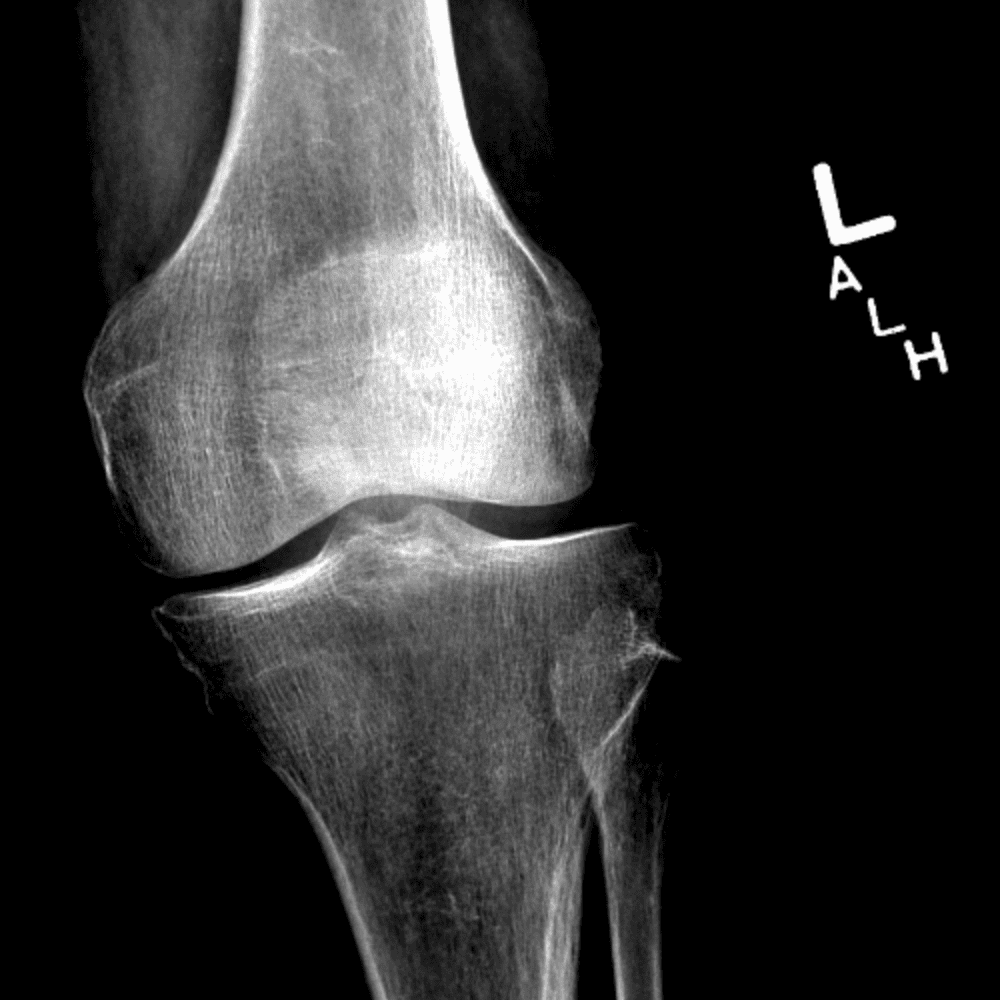

Simula o plantão incluindo casos sutis ou difíceis e alguns normais.